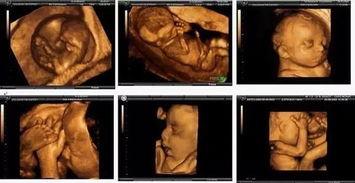

B超,全称超声波检查,是一种无创的医学检查方法。通过B超,医生可以观察到胎儿在母体内的发育情况。而B超胎动视频,则是将这一过程以动态的形式呈现出来,让准妈妈们能够直观地感受到宝宝的成长。

想象当你看到屏幕上那个小小的身影在妈妈肚子里翻滚、踢腿、挥动手臂时,是不是觉得既惊讶又感动呢?这就是生命的奇迹,一个全新的生命正在你的呵护下茁壮成长。

B超胎动视频不仅能够让你看到宝宝的可爱模样,还能记录下宝宝成长的每一个瞬间。从最初的胎芽,到后来的胎儿,再到出生后的宝宝,这些珍贵的画面将成为你一生中最宝贵的回忆。

随着科技的不断发展,B超胎动视频已经越来越普及。如今,许多医院都配备了先进的B超设备,能够为准妈妈们提供高质量的胎动视频。

这种科技与爱的完美结合,让准妈妈们能够更加直观地感受到宝宝的成长,同时也为医生提供了更准确的诊断依据。可以说,B超胎动视频是现代医学的一大进步。